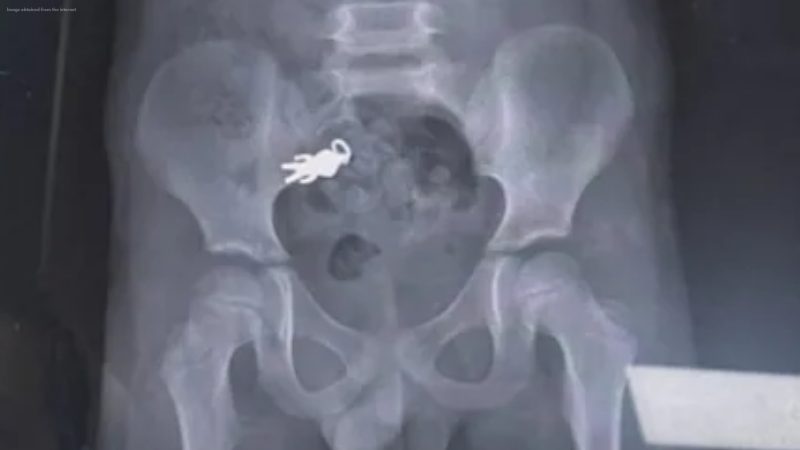

A 7-year-old boy accidentally swallowed a small Ultraman keychain while snacking and watching TV last Saturday, sparking a wave of online amusement after his family shared X-ray images showing the toy inside his stomach.

The boy, from Yilan, reportedly swallowed the 2.8 cm × 1.4 cm keychain while distracted by a TV show. Alarmed, his family rushed him to Luodong Boai Hospital, where doctors confirmed via X-ray that the toy had reached his small intestine. Fortunately, he remained healthy, and no surgical intervention was required. Medical staff will monitor him to see if the toy passes naturally.

The boy’s family humorously placed the keychain next to the X-ray and labeled it “Ultraman himself,” prompting widespread laughter online. Social media users reacted with amusement, commenting things like: “Can I frame this X-ray? So cool! 🤣” and “Ultraman is almost exiting!”